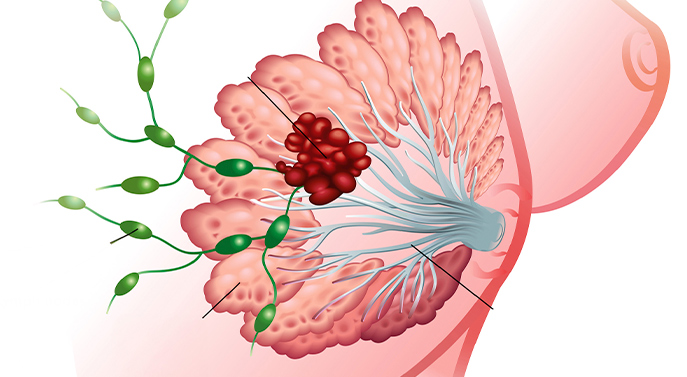

O carcinoma lobular invasivo (CLI) é um tipo de câncer de mama que se origina nos lóbulos mamários, responsáveis pela produção de leite.

Representa cerca de 5% a 10% dos cânceres de mama invasivos e tende a ser bilateral, afetando ambas as mamas.

Este tipo de tumor pode ser mais difícil de detectar em exames de imagem devido ao seu crescimento difuso. Geralmente ocorre em mulheres após a menopausa, mas pode surgir em qualquer idade.